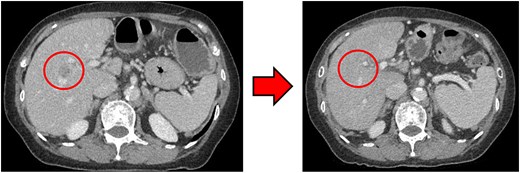

Computed tomography

Computed tomography (CT) revealed wall thickening of the descending colon with increased pericolic fat tissue density (Fig. 2). Multiple enlarged regional lymph nodes were observed. Liver metastases were identified in the liver S5/7 and S6 (Figs 3 and 4). The S5/7 lesion was located near the anterior branch of the portal vein and the right hepatic vein.

(Left: Before NAC) Wall thickening of the descending colon with increased pericolic fat tissue density. (Right: After NAC) Significant shrinkage of the primary lesion.

(Left: Before NAC) Liver metastasis in the liver S5/7. It was located near the anterior branch of the portal vein and the right hepatic vein. (Right: After NAC) Liver metastasis in the liver S5/7. Complete resolution of the S5/7 liver metastasis.

After four cycles, CT revealed significant shrinkage of the primary lesion (Fig. 2), disappearance of lymph node metastases, and complete resolution of the S5/7 liver metastasis (Fig. 3). The S6 lesion had decreased substantially, with near-complete necrosis (Fig. 4). Tumor markers declined (CEA 16.7 ng/mL, CA19–9 31.1 U/mL).